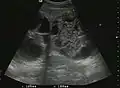

The ultrasound appearance is a well defined lesion, with very thin, almost unapparent walls, without circulatory signal at Doppler or CEUS investigation. The content is transonic suggesting fluid composition. The presence of membranes, abundant sediment or cysts inside is suggestive for parasitic, hydatid nature. Posterior from the lesion the acoustic enhancement phenomenon is seen, which strengthens the suspicion of fluid mass. They typically displace normal liver vessels but no vascular or biliary invasion occurs.

Liver cyst -

Hydatid liver cyst. Diagnostic criteria are the presence of membranes and sediment inside.